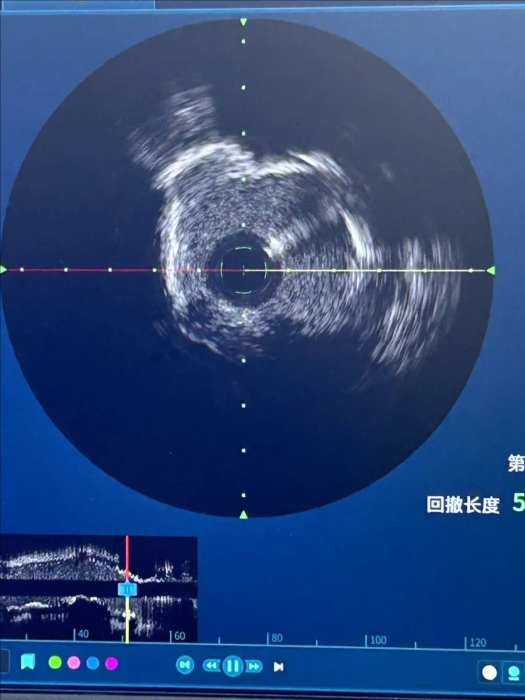

患者71歲,男性,合并長期糖尿病、腎病、高血壓病史,近1周反復(fù)出現(xiàn)活動后胸悶、氣短。入院后,行冠脈造影提示,前降支近段嚴(yán)重狹窄,且存在嚴(yán)重鈣化。血管內(nèi)超聲(IVUS)顯示前降支近中段彌漫性鈣化,近段270°環(huán)形鈣化,像“石頭”一樣硬,給介入治療帶來了很大難度。

振波球囊擴張前的LAD6段IVUS的圖像

振波球囊擴張后的LAD6段IVUS的圖像

術(shù)中,在局部麻醉下通過橈動脈通路,首先在血管內(nèi)超聲(IVUS)輔助下使用振波球囊對血管鈣化部位進(jìn)行連續(xù)沖擊波治療,終于使鈣化斑塊碎裂,擴大了管腔面積,順利植入支架并充分膨脹。至此,治療順利完成。